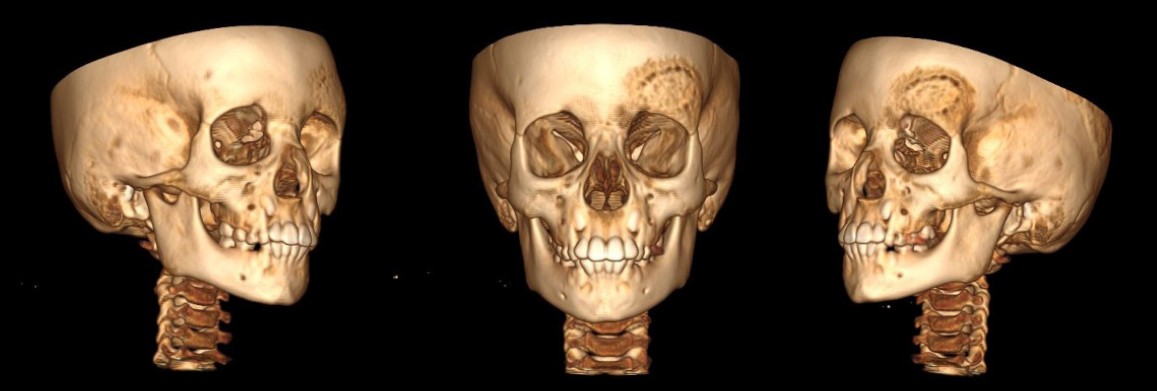

Treatment

A split auto-graft taken from the left parietal bone was remodeled to fit in the left frontal bone defect then fixed by mini-plate and mini-screw following by placing and fixing the internal cortical graft in the defect of the left parietal region (Figure 10).

Observation

In the postoperative period, the patient received antibacterial, infusion and symptomatic therapy. Healing by primary intention with the bone configuration looking normal. The patient was discharge home after 2 weeks from the operation day. He was monitored each year in RCCH by a follow up MSCT of skull. Recurrent episodes of this condition was revealed in 2022. MSCT showed evidence of bone regeneration and recurrence, with “hazy ground glass” appearance again in the same treated area in the left frontal bone region. (Figure 11). In 2025, a MSCT has been done again, and we noticed fast progression of FD in the same affected area (Figures 12, 13).

Fig. 10. A split auto-graft. a — MSCT with three-dimensional reconstruction check-up, one day after the operation; b — Postoperative axial CT image

A 9 year old girl presented volume formation and growth in the right frontal bone in the winter of 2021. Due to no complain by this formation, the patient did not received any treatment back then. The patient was admitted to the RCCH for the first time for examination and treatment 2022, where a MSCT was done, due to notable facial asymmetry.

Diagnosis

MSCT of the skull shows monostatic fibrous dysplasia in the right frontal bone (5x5 cm). A focus of fibrous dysplasia with damage to the frontal bone and orbital roof was revealed. Additionally, edema and deformity in the right frontal bone was observed (Figure 14).

Fig. 14. The edema and deformity in the right frontal bone. a — 3D computed tomography image shows increased dimensions of the right frontal bone; b — axial computed tomography image with expansion of right frontal bone

Fig. 15. Post-operation MSCT with three-dimensional reconstruction check-up

A split graft from the cranial vault was planned. A 5×5 cm fragment was taken from the adjacent area of the unchanged frontal bone, which was subsequently split into 2 fragments with the return of the inner cortical plate to the donor area, and the outer cortical layer was cut into 3 fragments and re-modeled. The graft fragments were fixed to each other and to the skull bones (Figure 15).